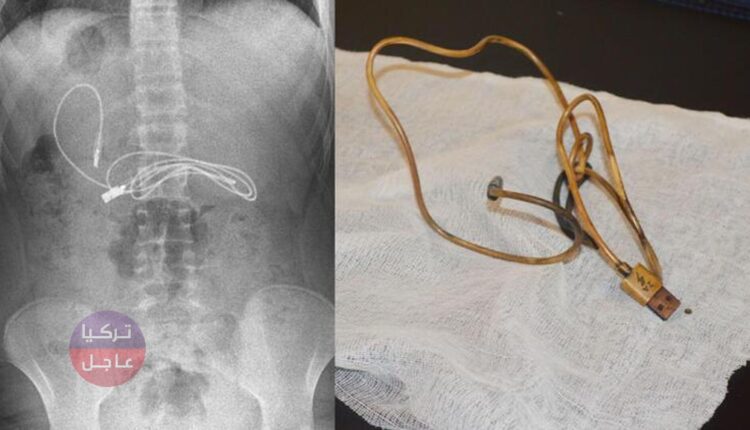

نقلت عائلة تركية في ديار بكر صبيًا يبلغ من العمر 15 عامًا ،كان يعاني من القيء والغثيان ، إلى المستشفى، وتبين وجود مشبك وكابل شحن في معدته.

وبحسب ما نقلته وكالة دوغان التركية، أن الأطباء في المشفى صدموا عندما شاهدوا الصور الشعاعية للكابل الذي انتقل طرفه الى الأمعاء، وتقرر نقل المريض الى آلازيغ بسيارة إسعاف.

بعد وصول المريض إلينا ، تم عمل الاستعدادات الأولية ، وبعد فترة الصيام المطلوبة ، خضع المريض لعملية المنظار. حيث تمت إزالة الكابل الموجود في المعدة عن طريق التنظير الداخلي. من الواضح أننا واجهنا صعوبة في إزالة الكابل لأن أحد طرفي الكابل قد مر إلى الأمعاء الدقيقة. بعد اكتمال الإجراء بنجاح ، تم إرسال المريض إلى منزله بصحة جيدة “.

صور من الخبر: